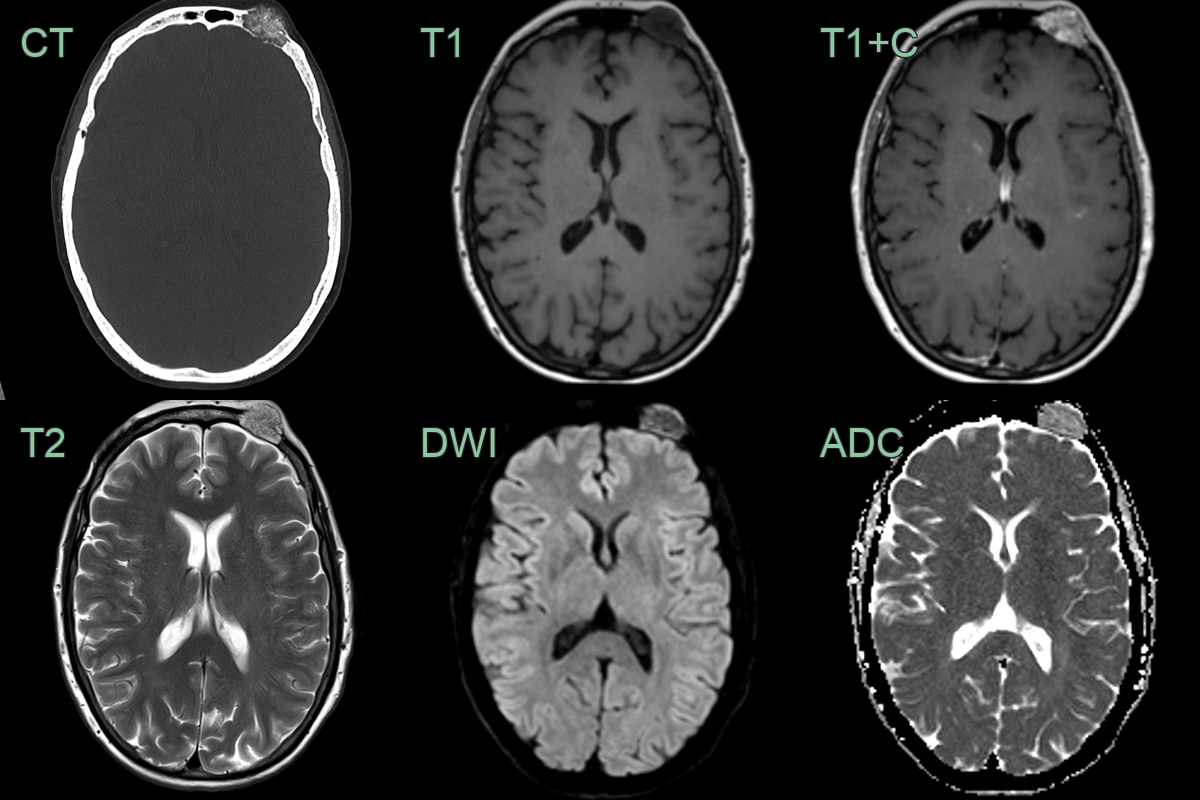

• A 40-year-old patient presented with an enlarged forehead lump.

• Imaging showed a partially calcified avidly enhancing intraosseous lesion in the left frontal bone.